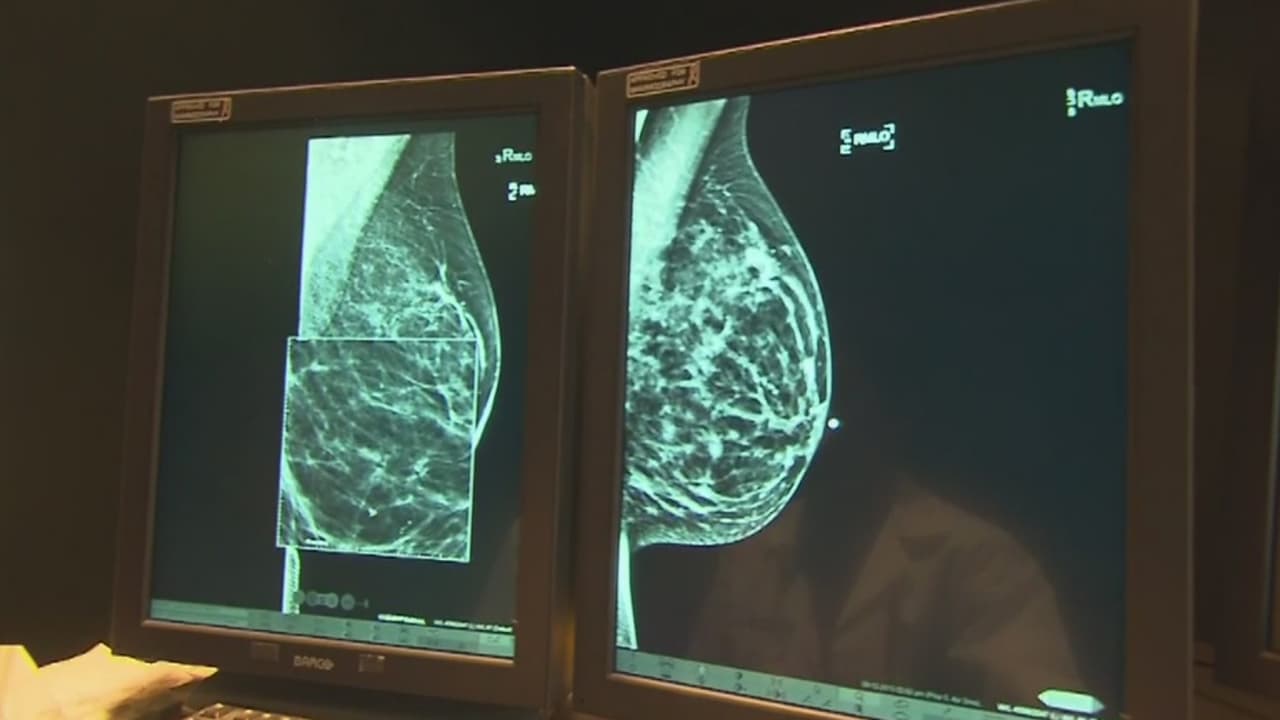

Una nueva investigación asegura que hasta el 70% de las mujeres que padecen esta enfermedad pueden librarse de someterse a quimioterapias. Una de cada ocho mujeres padece este tipo de cáncer, convirtiéndolo en uno de los más comunes entre la población femenina. La doctora Anneliese González, oncóloga de UTHealth, explica de qué se tratan los nuevos avances científicos sobre la enfermedad.